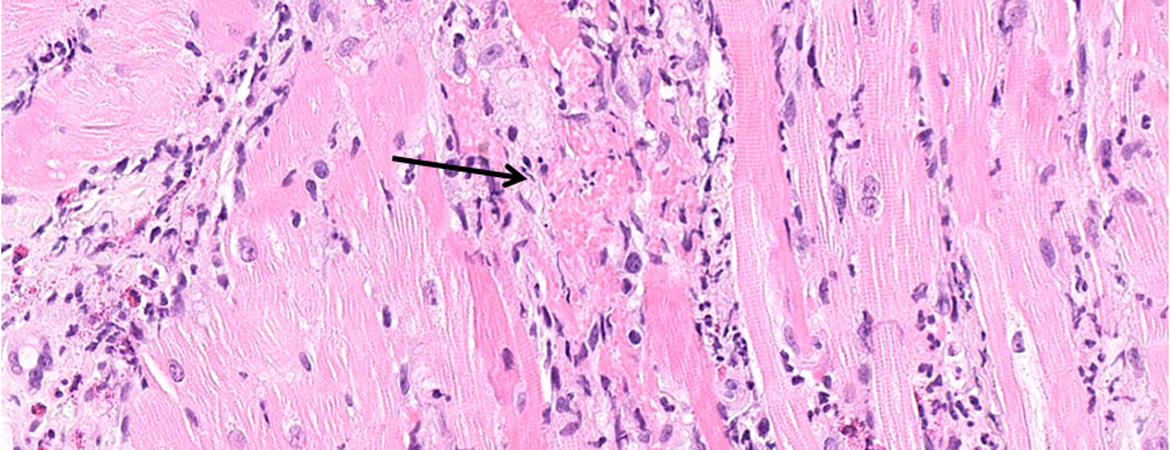

Summary

A 22-year-old male with a typical history of pauci-symptomatic COVID-19 3 weeks earlier, confirmed by positive serology for SARS-CoV-2 (IgG), was admitted to the intensive care unit because of severe myocarditis with refractory cardiogenic shock that required extracorporeal life support. Due to a clinical presentation suggestive of Kawasaki-like disease with coronary aneurysm and severe systemic inflammation, intravenous immunoglobulins were administered in combination with tocilizumab. The initial clinical course was favourable with these treatments. However, the patient subsequently developed a severe mononeuritis multiplex leading to bilateral foot drop, which required intensive immunosuppressive therapy (corticosteroids, cyclophosphamide and rituximab). The clinical presentation meets the criteria for multisystem inflammatory syndrome associated with SARS-CoV-2, but includes very severe organ damages. Early recognition, a multidisciplinary approach and aggressive therapeutic intervention can lead to a favourable outcome.